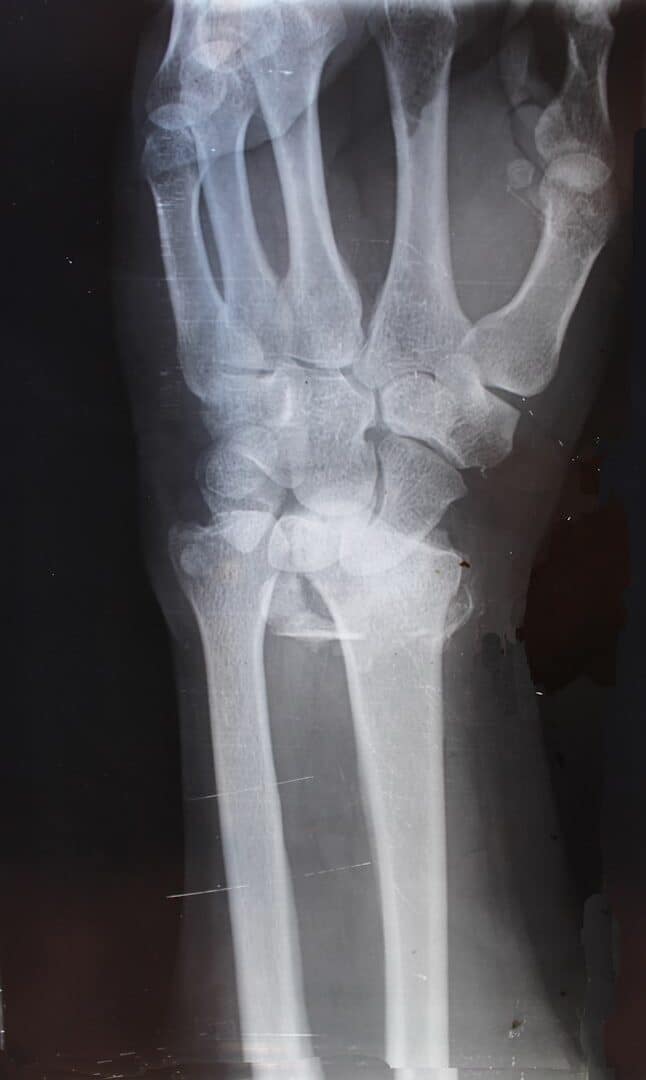

Hand and wrist fractures will be diagnosed during a consultation with Dr. Das. A physical examination will be performed, and X-rays will be requested to confirm bone fracture. Additional imaging tests such as CT scans and MRI may be needed to determine the severity of the condition.

At The Hand & Plastic Surgery Center of Katy, our hand surgeons are experienced in treating all types of upper extremity fractures including small joint finger fractures, metacarpal fractures, scaphoid and other wrist fractures, as well as distal radius fractures. They will work with you to obtain the proper diagnosis and determine a tailored treatment plan that fits your needs.

Treatment options for hand and wrist fractures include non-surgical solutions and surgical interventions. A cast, splint, or brace may be used to realign the bone fragments without creating an incision.

For severe fractures, especially in cases where the bone has broken through the skin, screws, pins, staples, or plates may be used to hold the bone pieces together. If the bones are severely crushed, a bone graft may be performed to fill in the gap.